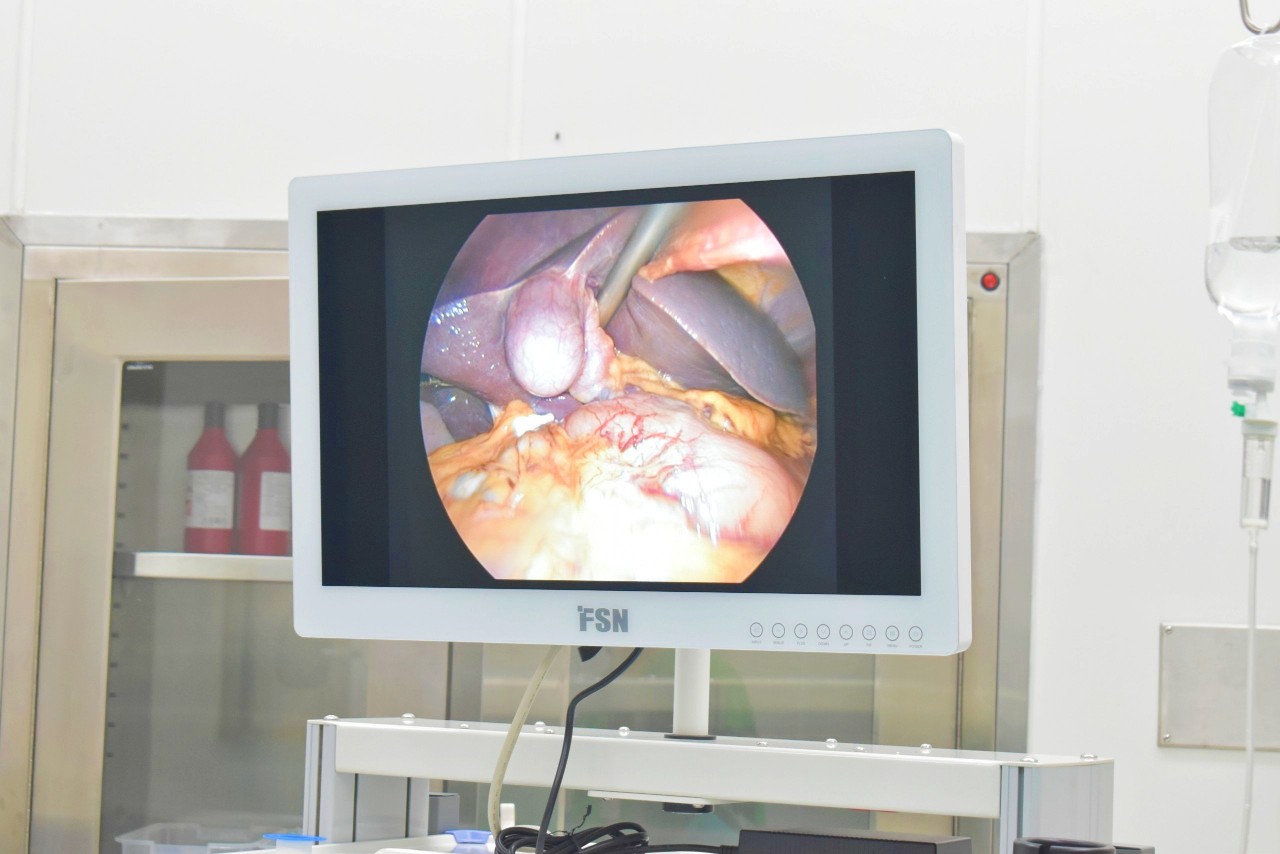

Hình ảnh túi mật trước khi cắt bỏ

Ekip do bác sĩ Huỳnh Thái Nam làm kíp trưởng đã thực hiện gây mê và sử dụng các thiết bị nội soi hiện đại để tiến hành phẫu thuật, cắt bỏ túi mật.